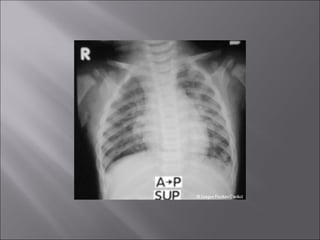

 Torso, vertebral, cranial, shoulder, hipradiograph: as if the patient is standing in an upright position.

 Decubitus chest and abdominal radiographs:so that the side of the patient that was positioned upward when radiograph was taken is upward on the hung radiograph.